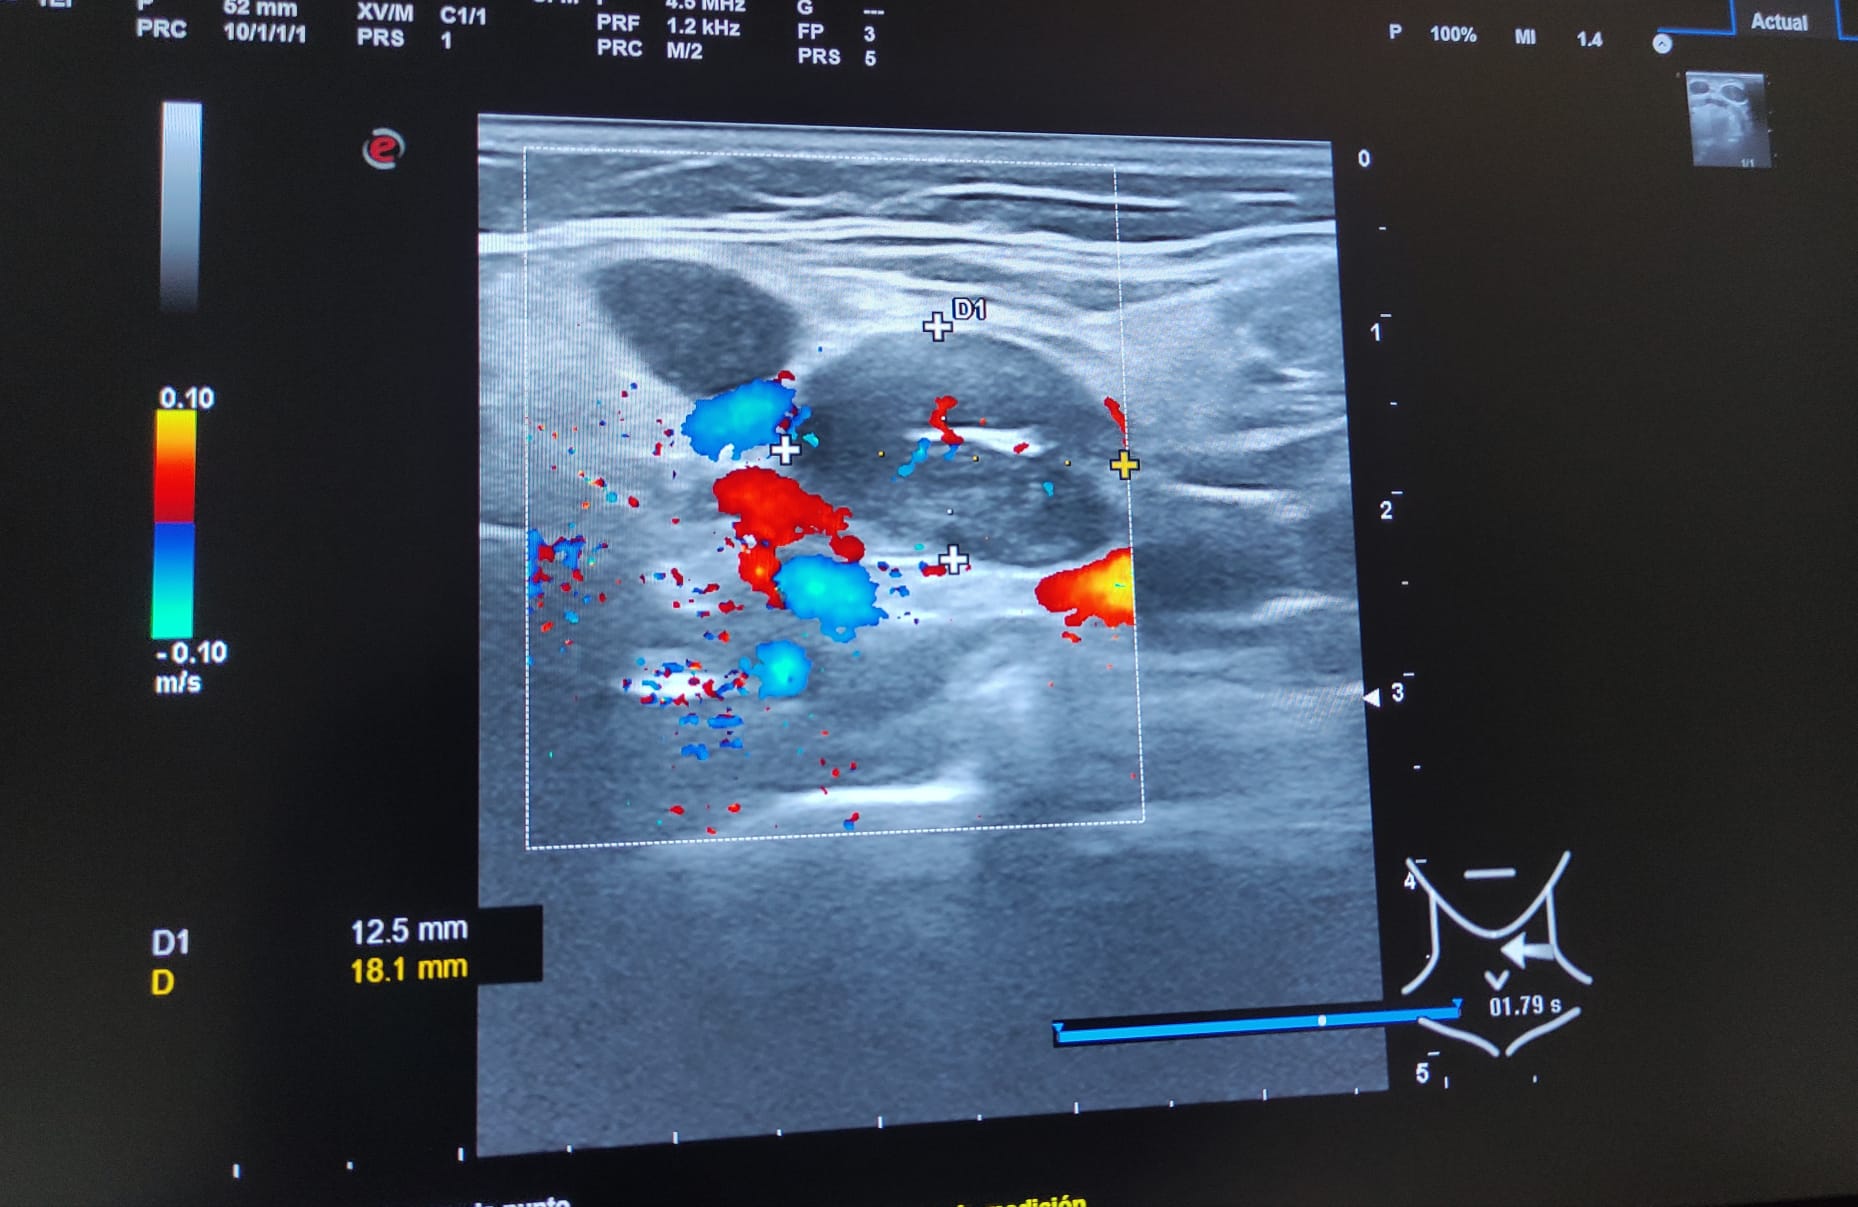

Múltiples adenopatías (más de 12) de varios tamaños siendo la mayor de 2 cm y de morfología redondeada, alguna sin hilio ni centro graso.

A los 3 meses se realiza nueva ecografía sin observar cambios significativos en las adenopatías ya visualizadas. Paciente permanece asintomática.